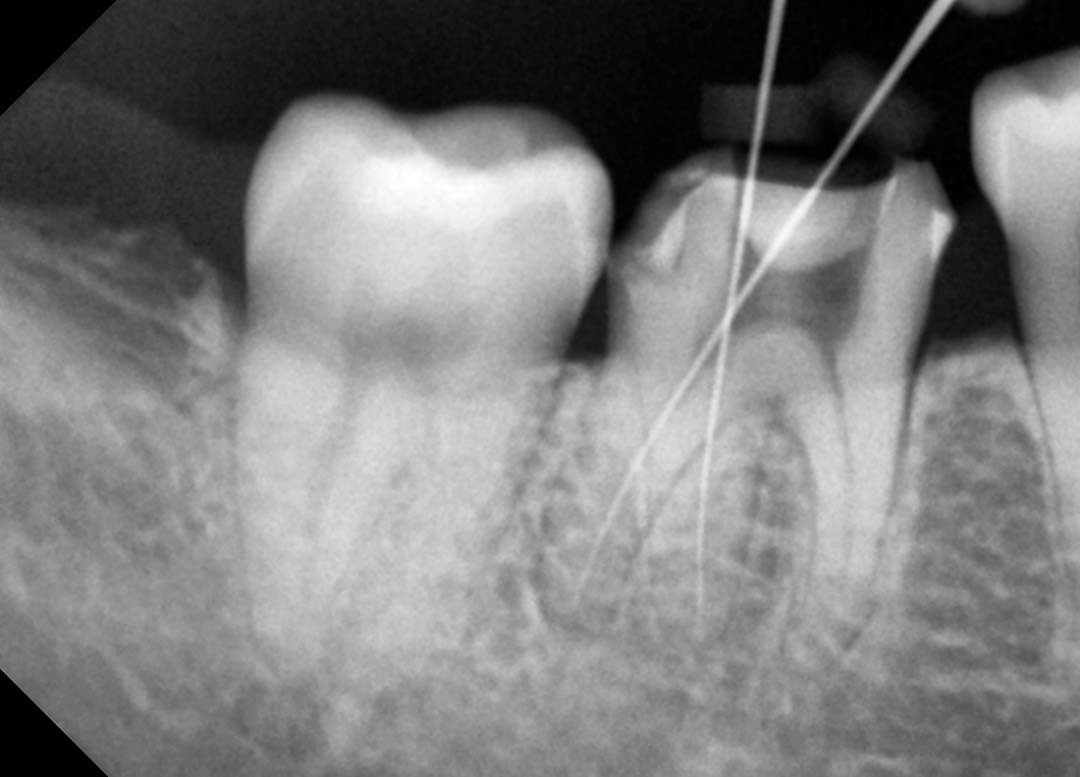

치료 중에 치아 1개에서 2개를 확인할 때 사용하는 포터블 엑스레이 사진

구내 엑스레이는 체어에서 치료 중 특정 치아 1~2개의 상태를 확인할 때 사용합니다. 목동나무치과에서는 바텍의 ezRay 포터블을 사용합니다. 다음은 신경 치료 중에 찍은 구내 엑스레이 사진입니다.

단일 치아나 소수의 치아를 국소적으로 촬영하는 장비입니다. 치료 중 특정 치아의 상태 변화를 실시간으로 확인하는 데 사용됩니다. 목동나무치과에서 사용하는 바텍의 ezRay 포터블은 가벼운 무게와 이중 차폐 기술로 환자와 의료진 모두의 안전을 확보합니다. 보통 '포터블'이라고 부릅니다.